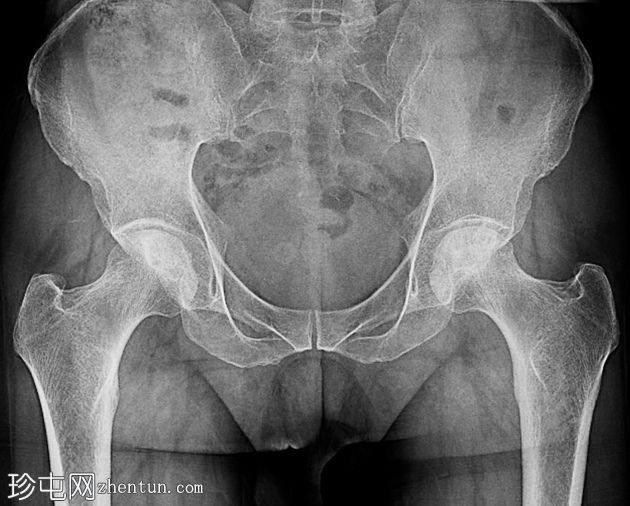

2.png

正位片

骨盆及双侧髋关节(前后位)

双侧股骨头均可见硬化区域,间杂透亮区。双侧可见可疑的软骨下透亮线(新月征)。髋关节间隙相对完整。未见明显的继发性骨关节炎改变。未见急性骨折或脱位。